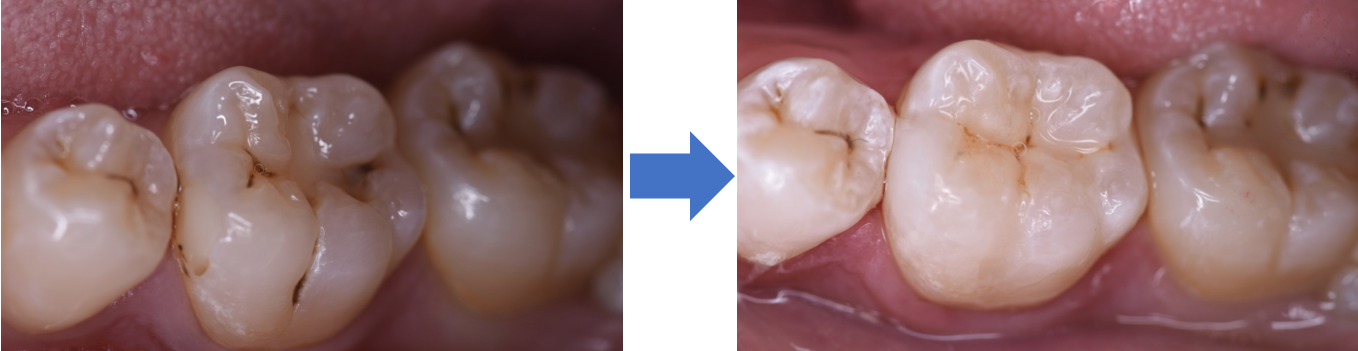

高い審美性を誇るダイレクトボンディング治療

当院では最新の歯科材料を使い、より審美性に優れたダイレクトボンディング治療をご提供しております。

当院では最新の歯科材料を使い、より審美性に優れたダイレクトボンディング治療をご提供しております。

ダイレクトボンディング専門で出張もしており症例も豊富です。

透明性の高い医療をご提供するためにも、術前・術後の写真をお見せしたりと、患者様が知りたいと思う情報を全て開示しています。

ダイレクトボンディング イメージ